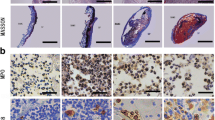

We observed the effects of mechanical extension in myoblasts induction. After isolating ADSCs, we assembled them into a tabularized bioabsorbable PGA scaffold. After being incubated in a dish for 7 days, the ADSCs–PGA constructs were then incubated in a reaction chamber of a bioreactor for 5 weeks. We produced a glossy tubular structure with a 6 mm lumen from the mechanical extension-stimulated group (Fig 4a, b).

a, b Gross view of tissue-engineered muscular tubes of urethra after dynamic cultured for 6 weeks. The tube diameter is ~6 mm. c Hematoxylin and eosin staining shows that PGA fibers are nearly degraded completely in the dynamic group. d Masson staining shows more collage fibers distributed evenly in the dynamic group. Many myoblast-like cells expressed desmin (e) and α-SMA (f) in the middle layer of engineered muscular tubes of urethra cultivated with mechanical extension stimulation

Histological evaluation of tissue microstructure

Using HE, Masson and immunohistochemical staining analyses, we discovered that the PGA scaffold adsorbed more quickly in extension-induced muscular tubes and these tubes exhibited increased expression of collagen fibers, desmin and α-smooth muscle actin (α-SMA) (Fig. 4). Desmin and α-SMA are markers of myoblasts, and collagen fibers are the main structural constituents of urethras. Therefore, our results showed that mechanical extension combined with chemical induction can generate myoblasts from ADSCs.